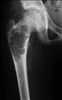

Malunited fracture of femoral neck

Coxa vara